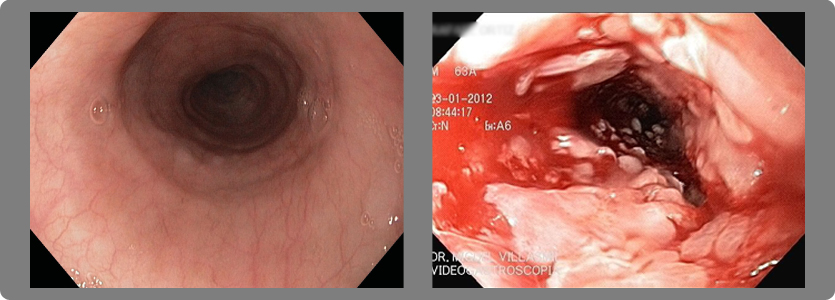

1- Esofagitis

Existen 4 grados diferentes de acuerdo a la severidad de las lesiones.

- Grado A:

Una o más úlceras no mayores de 5 milímetros que no se extiendan entre las crestas de los pliegues mucosos.

- Grado B:

Una o más úlceras mayores de 5 milímetros que no se extiendan entre las crestas de los pliegues mucosos.

- Grado C:

Úlceras que se extienden entre las crestas de uno o más pliegues mucosos pero que afecta a menos del 75% de la circunferencia

del esófago.

- Grado D:

Úlceras de la mucosa que afectan al menos 75% de la circunferencia del esófago.

2- Estrechez (estenosis) del esófago

Cuando la esofagitis es grado C o D se producen múltiples cicatrizaciones de la pared y eso origina retracción de la misma con la consiguiente estrechez del esófago y dificultad para tragar (disfagia).

Endoscopia superior:

Es un estudio mediante el cual se introduce por la boca del paciente un tubo flexible de menos de 1 centímetro de diámetro y se avanza progresiva y sucesivamente a través del esófago, estómago, hasta llegar al duodeno. Este instrumento contiene en su interior un haz de fibra óptica conectada a una cámara y a un monitor de alta definición que nos permiten ver con gran aumento el interior de los órganos estudiados. Contiene asimismo uno o más canales de trabajo por los cuales se pasan instrumentos que nos permiten tomar biopsias y ejecutar procedimientos terapéuticos. Así mismo es posible tomar fotos y videos de los procedimientos realizados.

Este estudio se realiza con el paciente en ayunas, bajo sedación especial, por lo que no se sienten molestias. Se realiza en aproximadamente 5 minutos.

Permite evaluar los daños en la mucosa del esófago producidos por el reflujo gastroesofágico y la presencia o no de hernia hiatal concomitante.